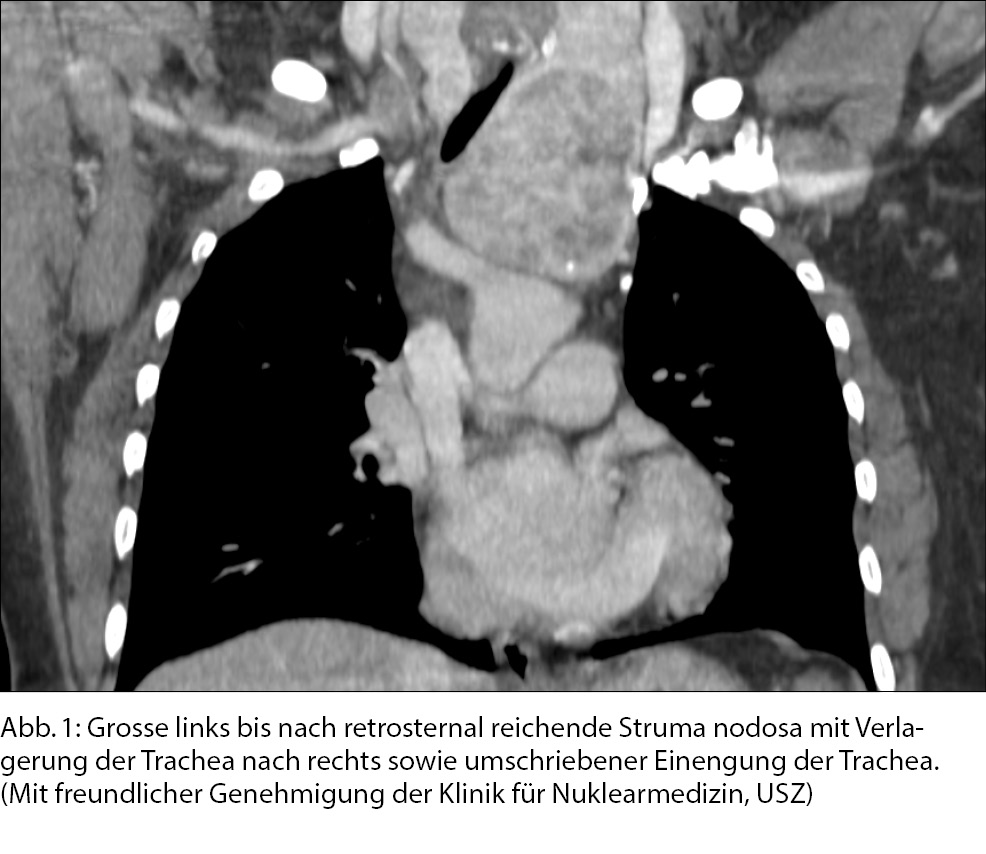

Hier geht es vor allem um eine Volumenzunahme der gesamten Schilddrüse im Rahmen einer grössenprogredienten Struma diffusa oder beispielsweise bei einer Thyreoiditis de Quervain. Auch bei grössenprogredienten Knoten (gut- wie auch bösartig) kann es zu einer Kompressionsproblematik im Bereich des Übergangs «Schilddrüse zu Luftröhre» kommen, welche Atemnot verursachen kann. Schilddrüsenknoten sind eine häufige Krankheit und ihre Abklärung und Therapie ist heutzutage standardisiert (5). Essentiell ist es, eine saubere Anamnese und einen körperlichen (Schilddrüsen-) Untersuch durchzuführen, um auf eine allfällige Kompressionsproblematik aufmerksam zu werden. Eine einfache Spirometrie (6) kann auch weiterhelfen in der Diagnostik.

Sollte sich eine obstruktive Problematik zeigen, welche zu einer Behinderung der Atmung führen kann, sollte dies anlässlich eines interdisziplinären Schilddrüsenboards besprochen werden, da je nach Ursache der Kompression unterschiedliche Therapien gewählt werden. Die Möglichkeiten reichen von der Operation über die Radioiod-Ablation bis hin zur Thermoablation von einzelnen Knoten, falls diese zytologisch als benigne abgeklärt sind.

Selten können auch maligne Veränderungen der Schilddrüse zu Lungenmetastasen und damit zu einer Beeinflussung der Atemfunktion führen. (Abb. 1)